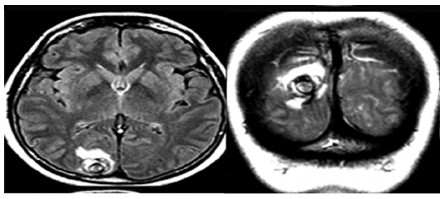

Dos años posteriores a la resección del MC consulta por cuadro de amaurosis fugax y fotopsias que se interpretan como equivalentes convulsivos parciales, se realizó RMN de cerebro que mostró múltiples lesiones a nivel corticosubcortical de aspecto en diana que se refuerza con contraste, pudiéndose corresponder a malformaciones arteriovenosas (AV), cavernomas, neoplasia o cisticercosis (Figura 2)

Se descartaron malformaciones AV y aneurismas por angiografía cerebral. La serología para cisticercosis fue negativa. La TAC de cuerpo entero no evidenció la presencia de otros tumores.